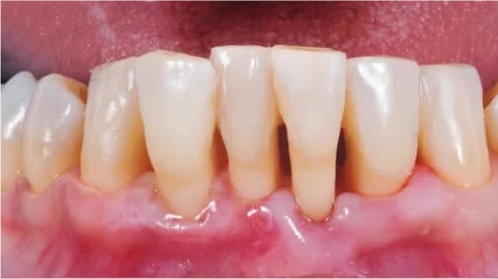

- เหงือกร่นลงอย่างชัดเจน จนมองเห็นคอฟันหรือรากฟัน ซึ่งทำให้ฟันดูยาวขึ้นผิดปกติ

อาการเหงือกร่นที่สังเกตได้ด้วยตัวเอง

อาการเหงือกร่นมักจะเกิดขึ้นช้าๆ จนบางทีคนไข้ลืมสังเกต จะมารู้ตัวอีกทีก็ตอนที่เหงือกร่นไปมากแล้ว ทางที่ดีควรใช้สัญญาณต่อไปนี้เพื่อสังเกตอาการตัวเอง

- ฟันดูยาวขึ้น เป็นสัญญาณที่ชัดเจนและดูได้ง่ายที่สุด เมื่อไหร่ก็ตามที่รู้สึกเหมือนกับว่าฟันยาวขึ้น ให้สงสัยว่าเหงือกร่นไว้ก่อนเลย

- เสียวฟันเมื่อทานของร้อน เย็น เปรี้ยว หวาน เพราะรากฟันที่ไม่มีเคลือบฟันป้องกันสัมผัสกับอาหารและเครื่องดื่มเหล่านี้

- เห็นรอยเว้าหรือร่องรอยต่อระหว่างเหงือกกับตัวฟัน เมื่อใช้นิ้วไปแตะดูจะรู้สึกว่าเหงือกเว้าลงไป